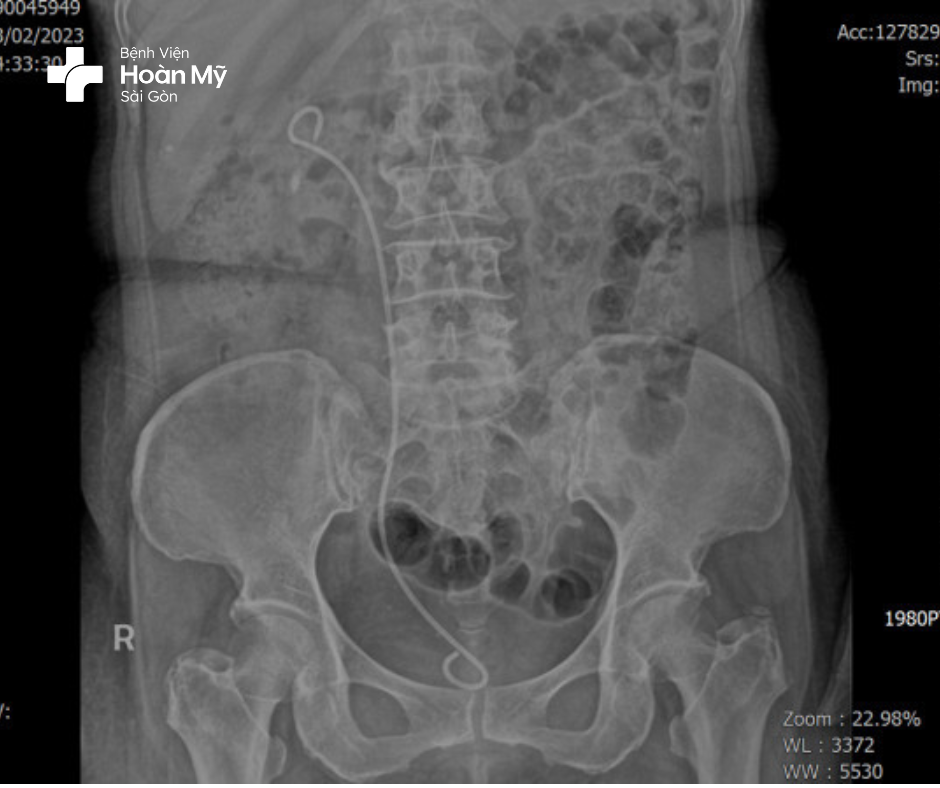

Hình 2: sau đặt sonde JJ

Sau 05 ngày hồi sức tích cực, chị A được chuyển khoa và lên kế hoạch tán sỏi qua da nhằm mục đích loại bỏ hoàn toàn viên sỏi thận Phải gây tắc nghẽn và nhiễm trùng. Sau tán sỏi qua da bệnh nhân hoàn toàn khoẻ mạnh, không còn đau hông lưng phải, được hướng dẫn theo dõi và tái khám để quản lý chặt chẽ tình trạng đái tháo đường, ống thông JJ thận Phải.